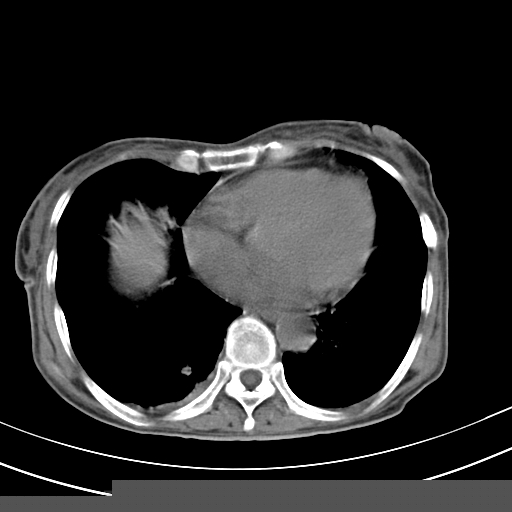

病人上腹部胀痛拌全身黄染八天

右侧少量胸水,胆囊增大,肝内胆管扩张,肝门部结构杂乱,建议增强。

右侧胸腔少量积液,右下叶结节灶,。

肝内胆管及胰管扩张考虑为胰头区占位,肝门淋巴结增多,肝内多发低密度影,考虑为转移。门脉高压,脾大,胆囊大。

肝内胆管及胰管扩张,胰头增大考虑为胰头区占位,肝门淋巴结增多,考虑为转移。建议增强,脾大,胆囊大,壁厚,慢性胆囊炎。胃壁好像也增厚,且有一肿物。

1)考虑胰头癌并胆系低位梗阻;建议行ct增强扫描检查。2)慢性胆囊炎。3)脾大。4)少量腹水。5)双侧少量胸腔积液。